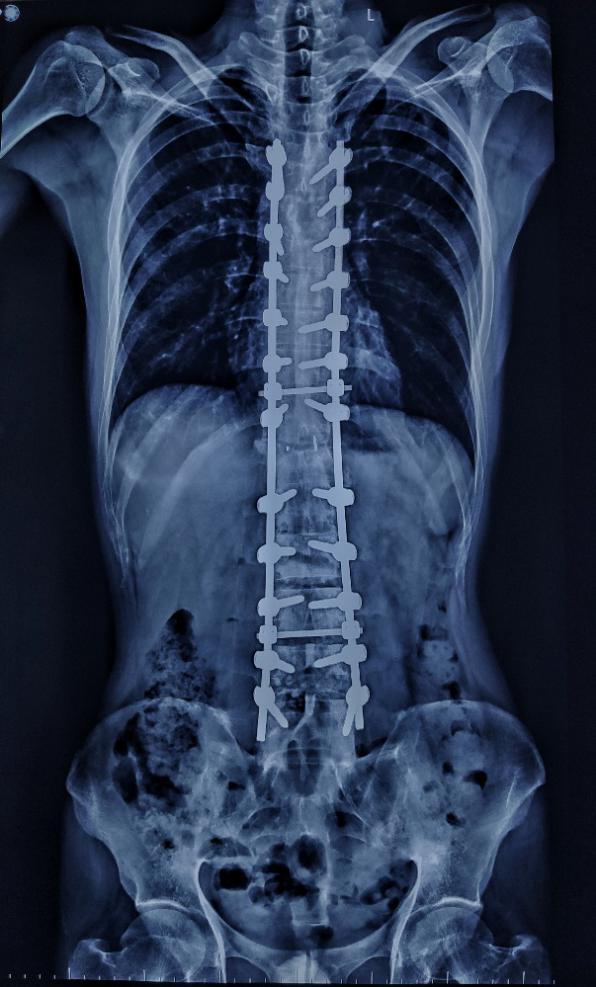

術后X線

截骨后的矯形也是手術的重中之重,陳劍銳充分考慮到截骨斷骨斷端的閉合及如何防止移位和固定的生物力學,加載負荷等問題,同時避免脊柱的短縮所導致的硬膜褶皺所帶來的雙下肢“癱瘓”的風險,術中不斷變化手術床的角度,恢復脊柱角度,矯形度數高達到50度左右。

術后,患者喚醒雙下肢活動良好,手術完美結束。患者體態明顯改善,目前患者恢復良好,身高長高十幾厘米,在支具保護下已行走自如,“背鍋”十年,終于挺直腰桿。